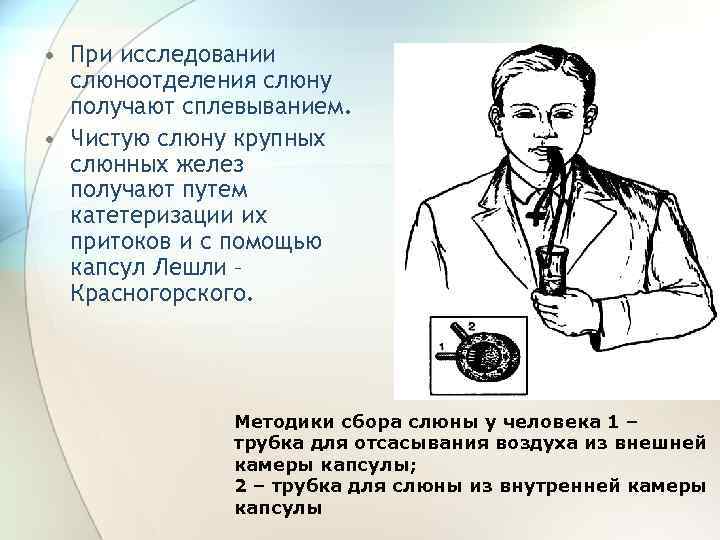

• При исследовании слюноотделения слюну получают сплевыванием. • Чистую слюну крупных слюнных желез получают путем катетеризации их притоков и с помощью капсул Лешли – Красногорского. Методики сбора слюны у человека 1 – трубка для отсасывания воздуха из внешней камеры капсулы; 2 – трубка для слюны из внутренней камеры капсулы